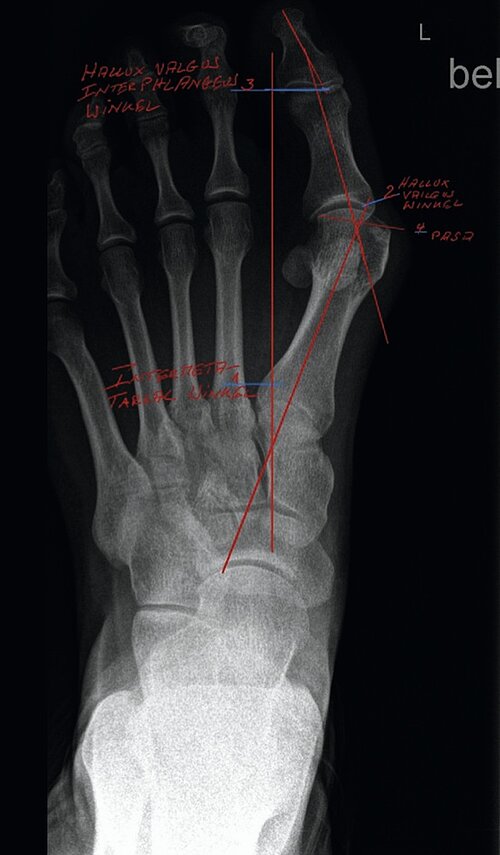

Die wichtigste bildgebende Diagnostik ist nach wie vor die Röntgenaufnahme des Fußes unter Belastung im a.p. (Abb. 2) und seitlichen Strahlengang sowie eine Aufnahme in 45°. Im Rahmen dieser Untersuchung werden der sog. Hallux valgus-Winkel, Intermetatarsalwinkel, Kopf-Gelenkwinkel sowie der Metatarsale-Index ermittelt [2,3]. Weiterhin wird die Knochen- und Gelenkstruktur zur Abklärung z. B. einer Arthrose (Gelenkverschleiß), Osteoporose, Osteonekrose, Osteoarthropathie etc. beurteilt. Als weitergehende Verfahren stehen die Kernspintomographie, die Computertomographie, digitale Volumentomographie (DVT) und/oder die Szintigraphie zur Verfügung.